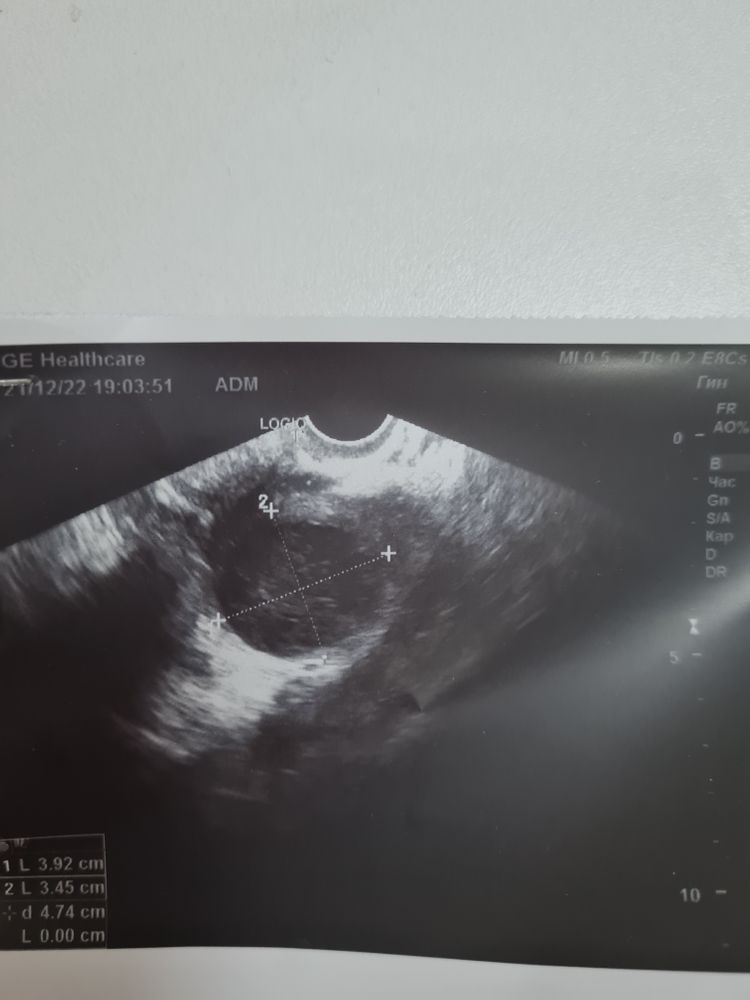

Irina в Зачатие 3 года Киста фолликулярная? Была сегодня на УЗИ, чуда не случилось. Видимо фолликулярная киста. Но 1% сомнений у врача возник. Может тут девочки что подскажете. Точно не было овуляции? Посмотрите еще 20 записей на эту тему Отменить Ответить Алина Не было. Лопается на 20-24 мм, у вас 39 мм, перерос. Бывает, ничего смертельного нет тут) 22.12.2022 Ответить Irina Алина, нет, но был и укол овитреля и инсеминация. То есть куча денег на ветер получается ☹️ 22.12.2022 Ответить Алина Irina, ой да вы что! тогда конечно( 22.12.2022 Ответить Мурочка Ирина, похожая ситуация у меня сейчас. Что у Вас было дальше с кистой? 03.03.2023 Ответить Объясните пожалуйста Тесты на овуляцию Чаты Беременных Выберите чат: Январята-2026 Февралята-2026 Мартята-2026 Апрелята-2026 Майчата-2026 Июнята-2026 Июлята-2026 Августята-2026